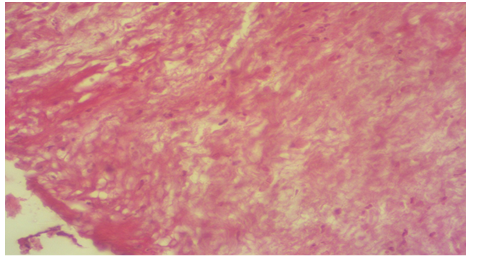

Photomicrography of T1 group at 30th days post operation showed thick scar tissue with presence of irregular connective tissue with inflammatory cells (H&E 100X).